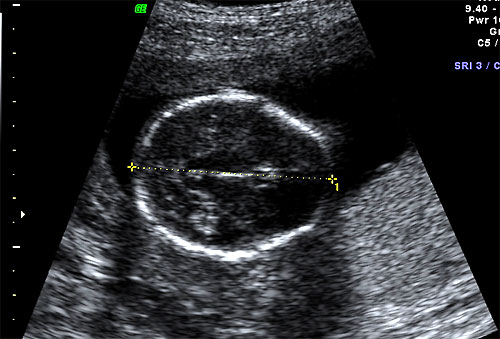

Normal BPD and HC at 16 weeks |

Normal 16 week OFD measurement |